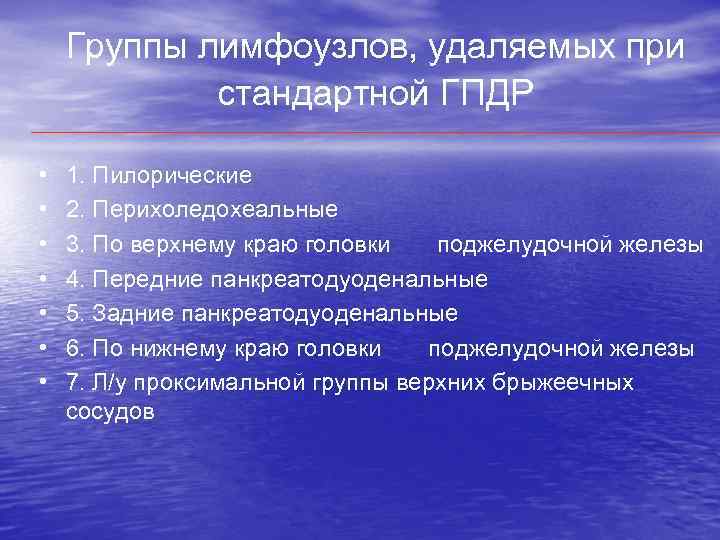

Группы лимфоузлов, удаляемых при стандартной ГПДР • • 1. Пилорические 2. Перихоледохеальные 3. По верхнему краю головки поджелудочной железы 4. Передние панкреатодуоденальные 5. Задние панкреатодуоденальные 6. По нижнему краю головки поджелудочной железы 7. Л/у проксимальной группы верхних брыжеечных сосудов